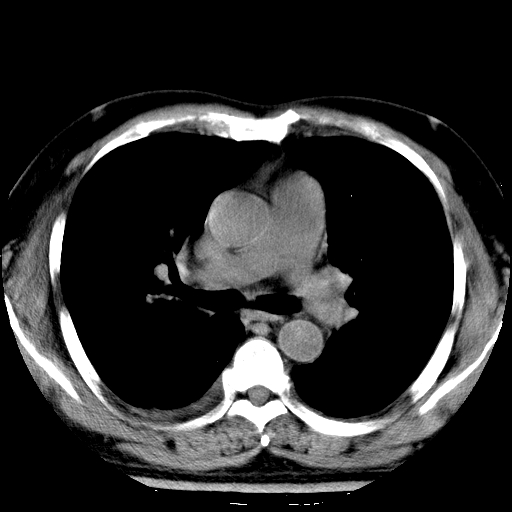

标题: CT21804:男,65岁,咳嗽、咳痰、发热5天。 [打印本页]

男,65岁,咳嗽、咳痰、发热5天。

慢支,肺心病

支持慢性支气管炎伴感染,双侧少量胸腔积液.

两肺间质纤维化,支扩合并感染,双侧胸腔积液

慢性支气管炎并感染,支扩,双侧少量胸腔积液.